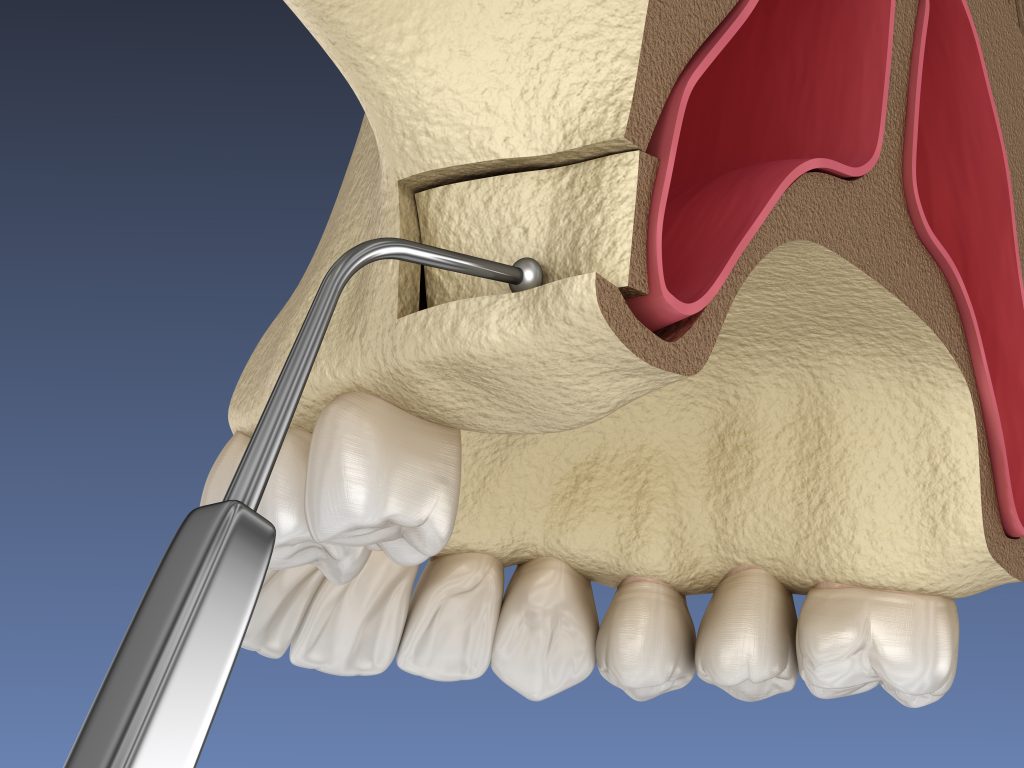

Le secteur postérieur du maxillaire est l’une des zones les plus complexes en implantologie. La résorption osseuse, souvent consécutive à l’extraction de dents ou à une longue période d’édentement, associée à la pneumatisation du sinus maxillaire, entraîne fréquemment un manque de hauteur osseuse. Dans ces cas, le geste chirurgical du Sinus Lift (ou élévation du plancher sinusien) devient la seule solution pour permettre la pose d’implants dentaires d’une longueur suffisante.

- Choisir la Technique Adéquate : Maîtriser les indications de la voie crestale (technique de Summers ou Ostéotomes, moins invasive, pour les petits déficits) et de la voie latérale (fenêtre osseuse, pour les greffes de grand volume). Le choix de la bonne technique est la première étape vers un succès chirurgical.

- Intégration de la Piézochirurgie : Les cours avancés intègrent l’utilisation du matériel de piézochirurgie, offrant une découpe osseuse sélective, minimisant le traumatisme et améliorant la sécurité du décollement de la membrane.